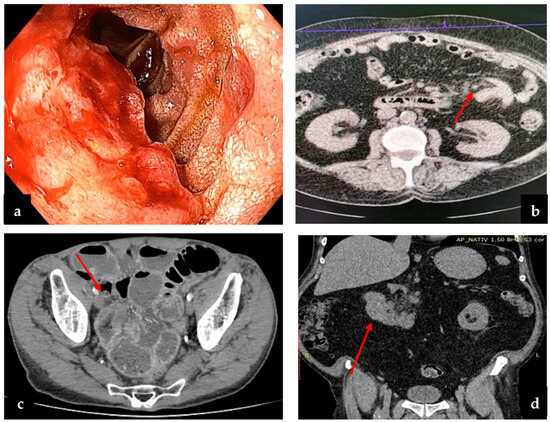

Regarding small bowel cancer diagnosis in the complication phase, it was mainly intraoperative in the first 3 years, but because of an increased CT scan usage in the emergency room in recent years (since 2020), small bowel cancer diagnosis was more often established preoperatively (Figure 3). The CT aspect in small bowel cancers can vary from bowel occlusion because of a stenosing tumor or intussusception, to bleeding or uncomplicated tumors (more frequent in the case of GIST). A CT exam was recommended in the emergency department for 16 patients, for 15 (93.3%) of whom the diagnosis of small bowel tumor was established (Figure 4b–d). Esophagogastroduodenoscopy (EGD, Figure 4a) was the preferred method for the diagnosis of duodenal tumors (four patients), and tumors located at the duodenojejunal angle (four patients), both as a primary method and also as a complementary method in the case of clinical or imagistic suspicion. Upper digestive endoscopy permits the visualization and biopsy of the lesion and also has a therapeutic role through tumoral stenting (duodenal tumoral stenting was performed in three patients with stenosis before the surgical step). The association of an endoscopic ultrasound may be useful in duodenal cancers for assessing in-depth invasion (pancreas, superior mesenteric pedicle). Although useful, the video capsule did not diagnosed any small bowel tumors in our patients. When acute complications (bleeding, occlusion, or perforation) were absent, MRI was recommended (Figure 5a,b) for the assessment of the possibility of resection (four cases of locally invading tumors). Intraoperative aspects of several small bowel tumors are presented in Figure 6, Figure 7 and Figure 8.

Figure 4.

(a) Endoscopic examination of a duodenal tumor; (b) CT exam of tumor bowel intussusception; (c) postcontrast CT scan, arterial phase, axial plane—there is a marked stenosing circumferential parietal thickening of a pelvic small bowel loop (arrow); (d) CT exam of duodenal tumor and perilesional lymph nodes.